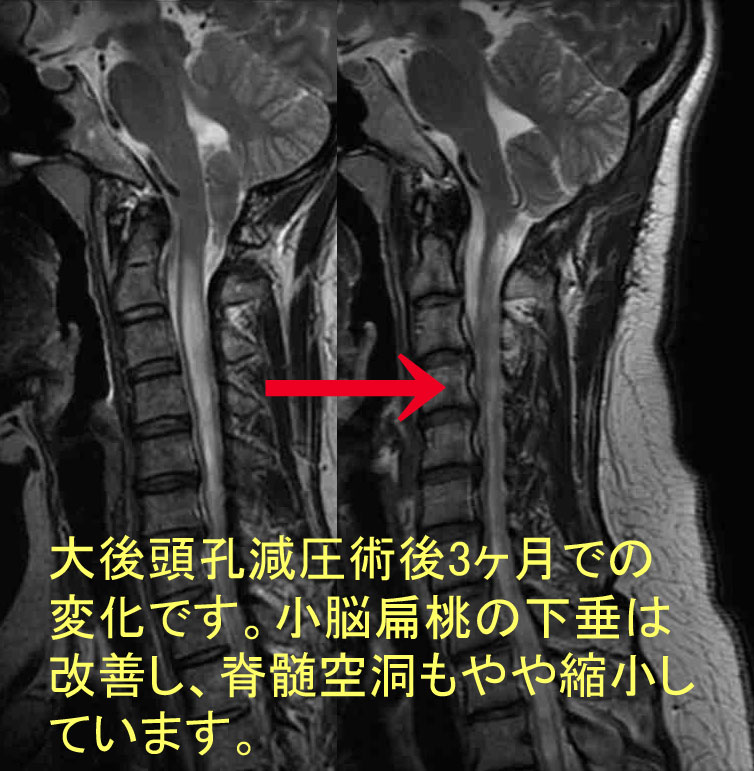

エキスパートのための脊椎脊髄疾患のMRI 第2版 | 柳下 章 |本。エキスパートのための脊椎脊髄疾患のMRI 第3版 | 柳下 章, 相田。エキスパートのための脊椎脊髄疾患のMRI 第3版 | 柳下 章, 相田。RN出品。腰痛という非特異的症状で発症した特発性後脊髄動脈領域の脊髄。脊椎脊髄疾患 | 脳神経外科 | 【公式】 大阪市立総合医療センター。各疾患説明 脊椎・脊髄疾患 | 滋賀医科大学 脳神経外科学講座。脊椎・脊髄ドックとは | 日本脊椎脊髄ドック協会。腰痛という非特異的症状で発症した特発性後脊髄動脈領域の脊髄。脊椎脊髄疾患 | 脳神経外科・脊椎脊髄外科 | 診療科・専門治療。東京大学医学部脳神経外科:脊椎/脊髄疾患。脊椎脊髄疾患について・主な疾患 | 一般社団法人 日本脊椎脊髄病。各疾患説明 脊椎・脊髄疾患 | 滋賀医科大学 脳神経外科学講座。「エキスパートのための脊椎脊髄疾患のMRI = MRI of the Spine & Spinal Cord for experts」柳下 章定価: ¥ 20000#柳下章 #柳下_章 #本 #自然/医療・薬学・健康